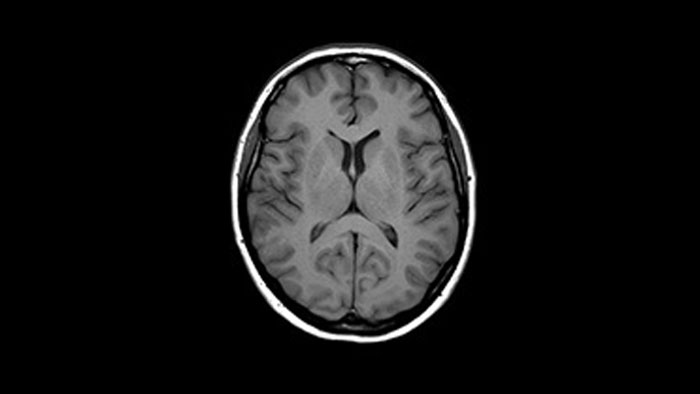

Enhanced diagnostic confidence in neuro oncology